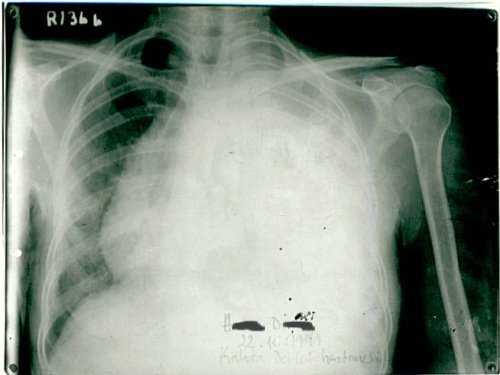

1992 yılında malign lenfoma teşhisi konulan 60 yaşındaki kadın hasta, immünomodülatör tedavi ile 6 ayda tam iyileşme sağladı. 10 yıllık takip sürecinde hastalık tamamen kontrol altındaydı ve hasta normal yaşamına döndü.

1992: 60 yaşındaki kadın hasta sol göğüs ağrısı ve öksürük şikâyetiyle başvurdu.

Plevral biyopsi yapıldı ve teşhis konuldu.

Biyopsi Sonucu: "Malign lenfoma"

2 Kasım 1992: Hasta uzman hekime getirildi.

Çok düşkün haldeydi. 4 mg immünomodülatör aşı sonrası ateşi 38.2°C'ye yükseldi.

Tedavi Protokolü: Haftada 6 gün, günde 4 mg immünomodülatör aşı

Röntgende belirgin düzelme görüldü. Tedaviye devam edildi.

Tümörün tamamen kaybolduğu görüldü.

Şikâyeti kalmamıştı ve immünomodülatör tedaviyi bırakması önerildi.

1998 (6 yıl sonra): Takipte remisyon devam etti

2002 (10 yıl sonra): Takipte remisyon devam etti